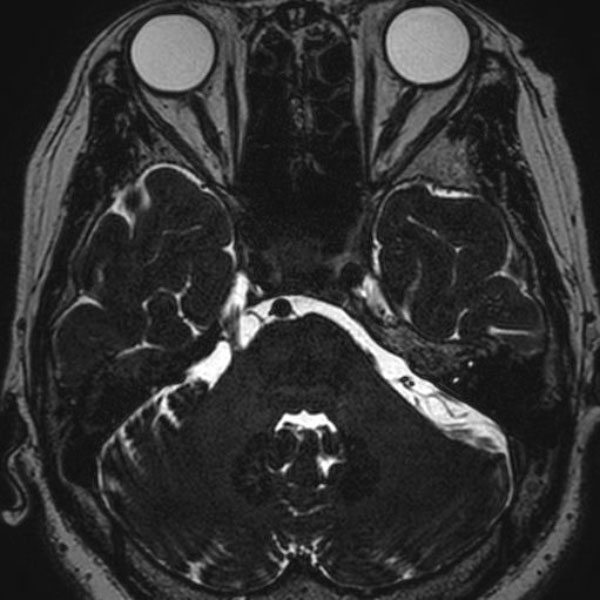

症例 '26年4月

No.

590

当院外来

'26年4月

60代

三叉神経痛第3枝領域

(顔面の痛みをとること)

手術前

減圧前

減圧後

術後血管撮影